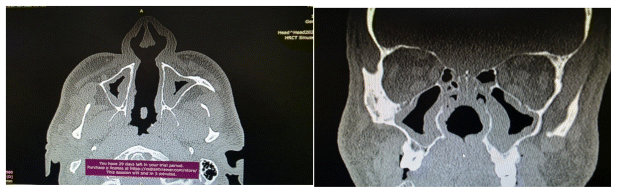

A non-contrast computed tomography (CT) scan of the head was performed. The imaging demonstrated destruction of the vomer bone. It revealed a distinct fistulous tract in the midline of the hard palate, with a slight deviation to the left, extending from the nasal cavity through the hard palate into the oral cavity (Figure 1).